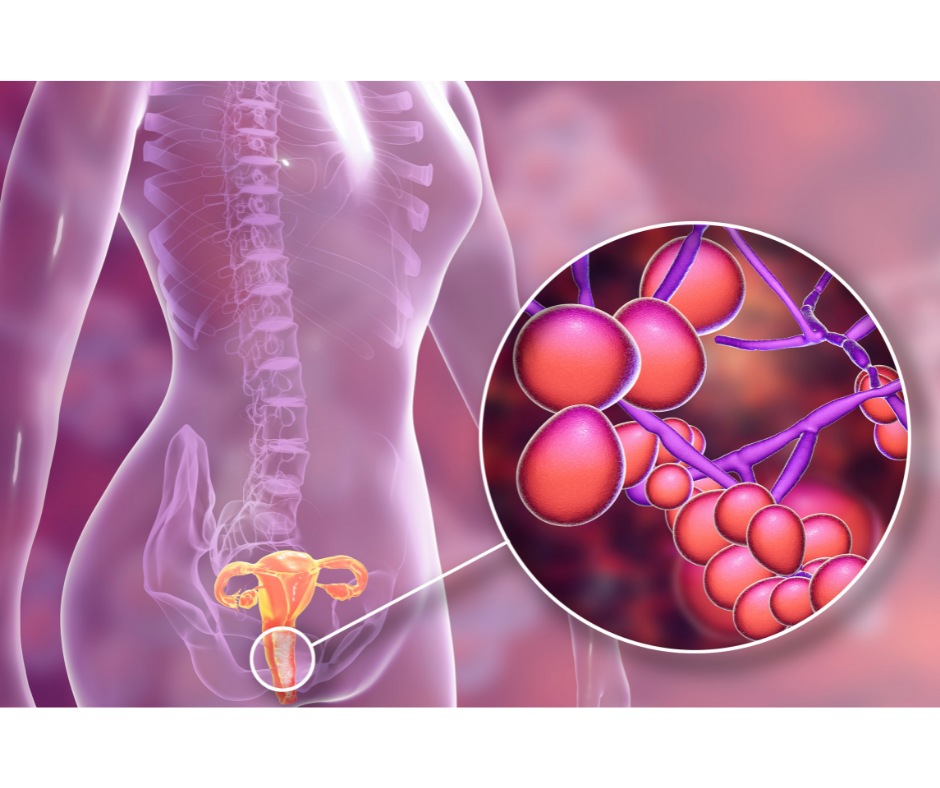

A urinary tract infection (UTI) is an infection of the